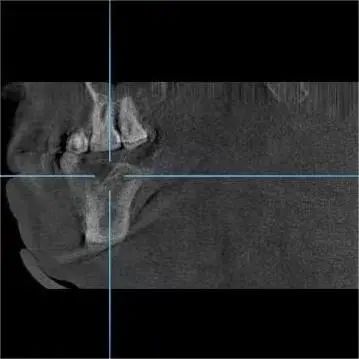

种植专家、口腔科杨彦春主任检查发现其口腔卫生环境较差,缺失的又是需要咀嚼的后牙,建议行种植修复手术。

术中,王先生血压、血氧稳定,仅用半小时,杨彦春主任顺利为其开展两颗种植牙手术。